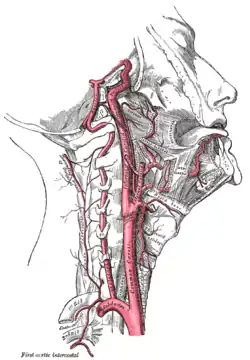

The common carotid artery is the large artery whose pulse can be felt on both sides of the neck under the jaw. On the right side it starts from the brachiocephalic artery (a branch of the aorta), and on the left side the artery comes directly off the aortic arch. At the throat it forks into the internal carotid artery and the external carotid artery. The internal carotid artery supplies the brain, and the external carotid artery supplies the face. This fork is a common site for atherosclerosis, an inflammatory build-up of atheromatous plaque inside the common carotid artery, or the internal carotid arteries that causes them to narrow.[3][4]

Atherosclerosis causes plaque to form within the carotid artery walls, usually at the fork where the common carotid artery divides into the internal and external carotid artery. The plaque build-up can narrow or constrict the artery lumen, a condition called stenosis. Rupture of the plaque can release atherosclerotic debris or blood clots into the artery. A piece of this material can break off and travel (embolize) up through the internal carotid artery into the brain, where it blocks circulation, and can cause death of the brain tissue, a condition referred to as ischemic stroke.[9]

The common carotid artery is the large vertical artery in red. The blood supply to the carotid artery starts at the arch of the aorta (bottom). The carotid artery divides into the internal carotid artery and the external carotid artery. The internal carotid artery supplies the brain. Plaque often builds up at that division and causes a narrowing (stenosis). Pieces of plaque can break off and block the small arteries above in the brain, which causes a stroke. Plaque can also build up at the origin of the carotid artery at the aorta.